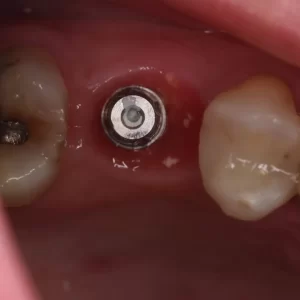

Hoje, compartilho um caso que exemplifica bem essa abordagem integradora: a reabilitação com prótese cimentada sobre munhão universal Neodent, destacando os resultados obtidos no perfil gengival após o uso de provisório para condicionamento tecidual.